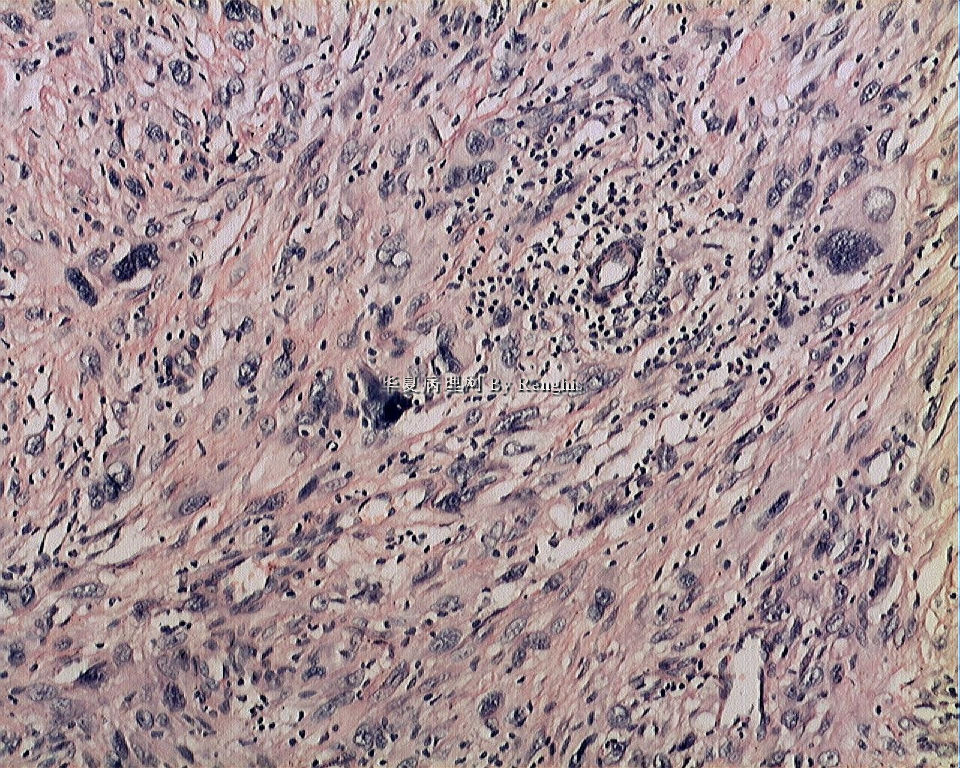

女,29岁,左大腿内侧肿物直径2.8cm,切面灰白、实性、质中,似有包膜。

本例就形态学而言不太符合纤维肉瘤,对于一个多形性和异型明显的肿瘤首先不考虑纤维肉瘤的诊断加上车辐状结构首先还是考虑纤维组织细胞肿瘤。

本人认同此例是一例比较典型的纤维肉瘤,瘤细胞程束状、鱼骨状及编织状排列,部分瘤细胞异型性明显,免疫组化vimentin阳性,SMA灶状弱阳性,desmin阴性,S100阴性,CK阴性,EMA阴性,余记不得了,明天看看再上传。